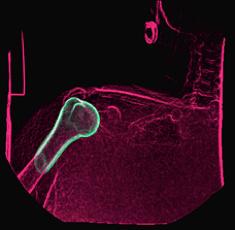

b) a) c) The Tic-Tac-Toe (TTT) radiofrequency head coil for 7T MRI Fig 1: in a), the implemented 16-channel TTT transmit RF coil; in b), the computational RF coil in c), the implemented RF coil with an 32-channel receive insert Fig. 2: The B1+ (magnetic field responsible for spin excitation) field homogeneity is highly degraded at 7T MRI due to a higher operational frequency (~297MHz). The TTT presents a more homogeneous field distribution when compared with the NOVA coil (a commercial coil) [1]. Measured Tic-Tac-Toe Measured Nova coil Regions with low B Simulated Tic-Tac-Toe B + maps in the brain: TTT vs NOVA RF coils TTT coil NOVA coil TTT coil NOVA coil Image comparison with the 32-channel NOVA commercial RF coil a) b) Fig. 3: In a), Turbo spin echo (TSE) sequence using the TTT coil with resolution of 0.4x0.4x2mm. In b), the same TSE sequence acquired with the commercial NOVA coil. In c), FLAIR sequence acquired with TTT coil with resolution of 0.7x0.7x2mm. In d), the same FLAIR sequence acquired with NOVA coil. The arrows point to regions of dark spots in the NOVA coil images and compare with similar regions on the TTT coil images [1]. c) d) High-resolution susceptibility weighted images showing cortical microvessels Fig 4 SWI images acquired at 0 2x0 2x1 5mm resolution In a) an axial slice of the whole brain image acquisition In b) and c), zoomed versions of a), detailing the micro-structures a) b) c) High resolution angiography without contrast agents 380μm a) b) Fig 5: Maximum intensity projection orientation and small vessels detectability isotropic image showing whole brain isotropic acquisition In d), 0 20mm are only detectable at higher resolution

Finger tapping task: activation of Functional MRI a) Diffusion MRI and fiber tracking Post-mortem a) a) b) Fig 7 In a), an structural MPRAGE image acquired at 0 75mm isotropic (skull removed using FSL package) In b), fiber tracking based on DTI acquisition, 64 directions, 1 5mm isotropic resolution The colors are defined for different orientations of the fibers Fig 8: In a), susceptibility weighted images acquired at 0 35mm isotropic, 32 min acquisition time, in a post-mortem brain fixated with formalin In b), a photograph of similar slice in the same brain Table 1: 7T MRI studies conducted at the RF Research Facility at University of Pittsburgh White matter legions (circle): Multiple Sclerosis study Stroke (circle): sickle cell disease study Automatic hippocampus segmentation: Midlife Neurocognitive Lacunar infarct (arrow): depression study White matter hyperintensities (arrows): Healthy Brain aging study (left) and Small Vessels disease in preclinical Alzheimer’s disease study (right) Fig 9: Sample of some studies listed in Table 1 using the developed 16 array (Fig a) There are 4 completed studies and 13 ongoing patient studies with approximated 2 000 patients scheduled FUTURE DIRECTIONS 64-channel Tic-Tac-Toe RF transmit coil for 7T MRI 0 Fig 10: In a), the 64-channel transmit coil computational modeling [2] To improve the field of view of the projector/monitor in fMRI studies, the frontal panels can be removed, resulting in a 56-channel coil In b), one assembled side of the coil In c), simulated B1+ field distribution: for an 8kW power amplifier capabilities (default in older 7T MRI scanners) a homogeneity (measured by the coefficient of variationCV) of 15 2% is achieved in the brain For an 16 kW power amplifier (available for the recently FDA approved Siemens 7T MAGNETOM Terra), an CV of 10 6% can be achieved in the brain 16 kW power amplifier: 8 kW power amplifier: a) b) c) max